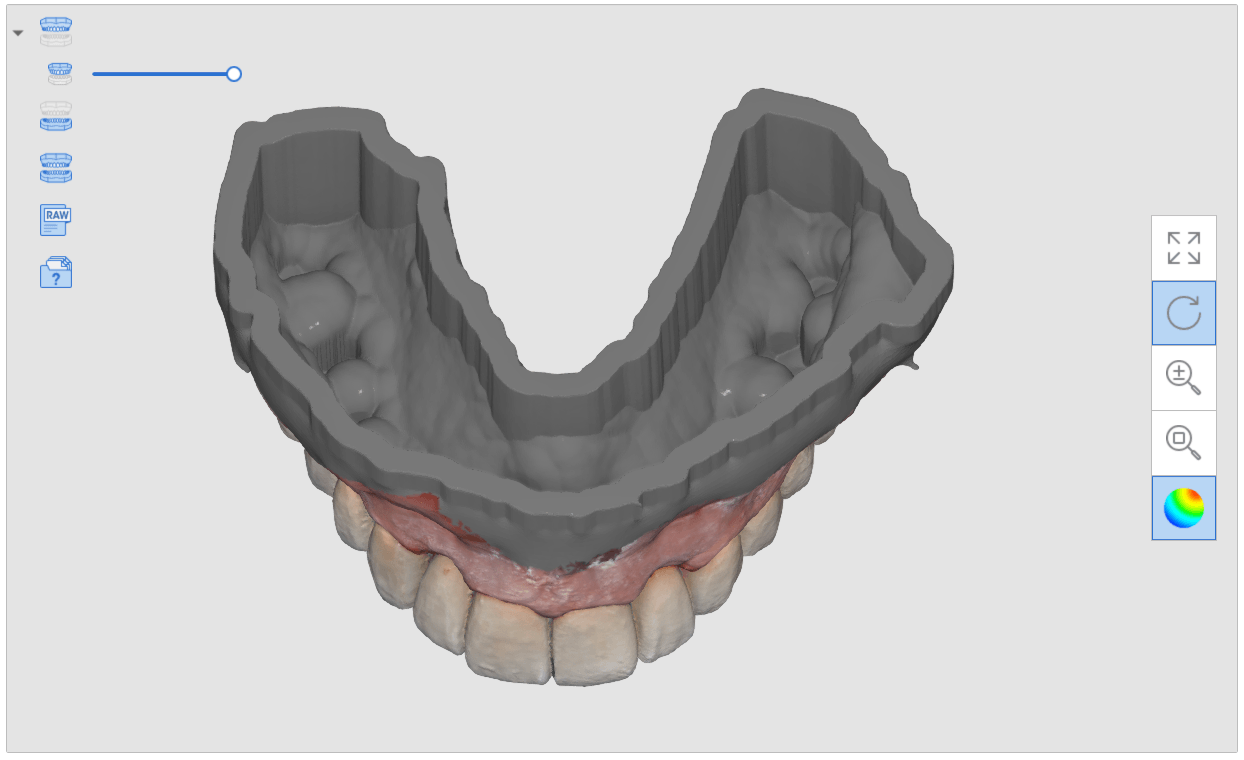

segmental imaging to building a master model

upper and lower models related to each other for design

Post op intra-oral scan with Medit i500 to capture irritated and hemorrhaging tissue (for demonstration purposes only)